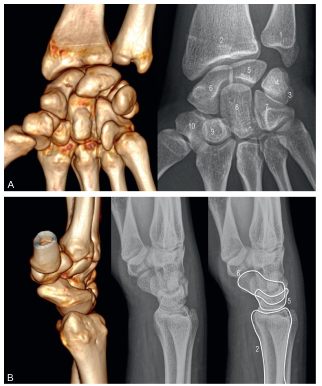

Fig. 74.6 Poignet : radiographies de face (A) et profil (B).

1. Ulna. 2. Radius. 3. Triquetrum. 4. Pisiforme. 5. Lunatum. 6. Scaphoïde. 7. Hamatum. 8. Capitatum. 9. Trapézoïde. 10. Trapèze.

Source : CERF, CNEBMN, 2022.